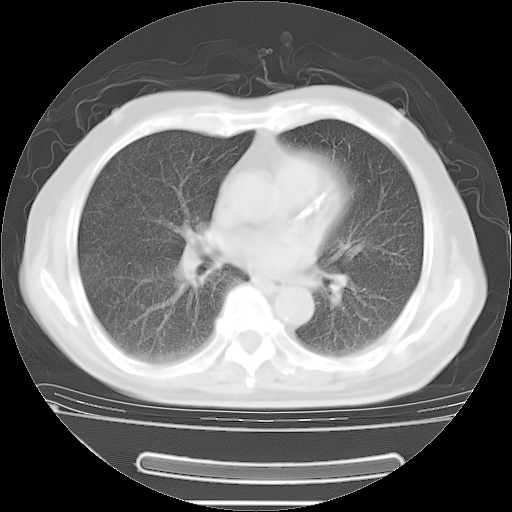

今天复查肺部CT,发现双肺广泛磨玻璃样改变。所以我把3月19日和5月9日相隔50天的肺部CT上传。请大家会诊。

2009年3月19日肺部CT片。

2009年3月19日肺部CT